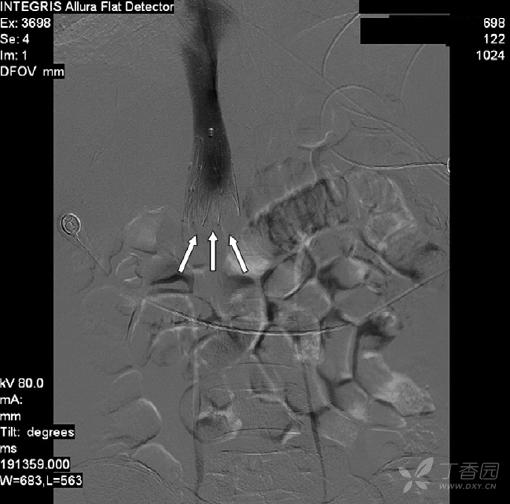

晚上7点,经颈静脉穿刺下腔静脉造影,于下腔静脉肾静脉开口上方放置滤器1枚,手术顺利。